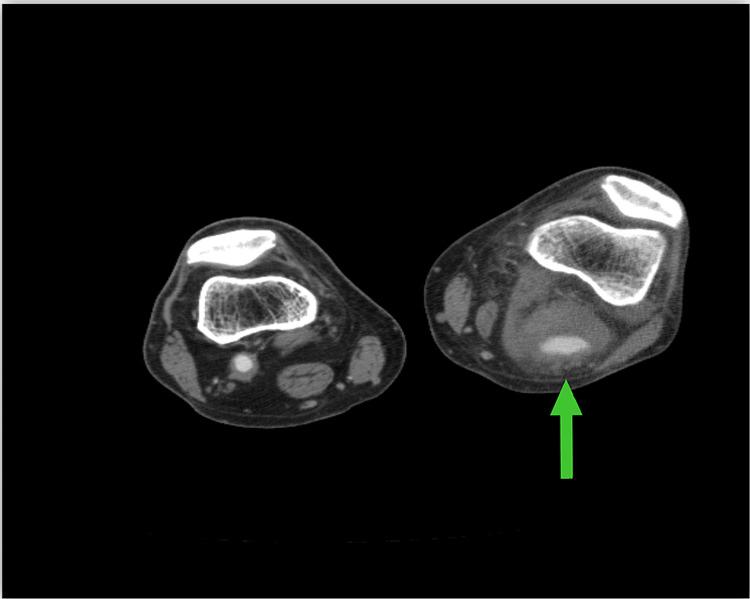

Popliteal artery aneurysms (PAAs) are the most common type of peripheral artery aneurysms. Mycotic aneurysms involving the popliteal artery are quite rare and can occur as either a primary infection or a secondary infection from another site. To our knowledge, there are no previous case reports on mycotic PAA in which was the primary etiologic pathogen. We present the case of a 55-year-old male who presented with complaints of lower extremity pain and swelling, malaise, and low-grade temperatures for two weeks and was found to have a PAA. He underwent left femoral-popliteal bypass grafting with expanded polytetrafluoroethylene (ePTFE) graft and ligation of the aneurysm. On postoperative day 10, he experienced acute swelling and pain in his lower extremity with foot drop and was found to have rapid enlargement of his aneurysm sac on imaging. He was returned to the operating room emergently where he underwent aneurysmectomy via a posterior fossa approach. Cultures and gram staining of the aneurysm sac were consistent with As noted above, this case of mycotic PAA was treated with standard vascular surgical techniques, yet it proceeded to enlarge acutely. PAAs that rapidly expand or rupture after surgical interventions may be a sign of infection.

腘动脉瘤(PAA)是最常见的周围动脉瘤类型。累及腘动脉的感染性动脉瘤非常罕见,可作为原发性感染或来自其他部位的继发性感染出现。据我们所知,以前没有关于以[具体病原体]作为主要病因病原体的感染性PAA的病例报告。我们报告一例55岁男性,他因下肢疼痛、肿胀、全身不适和低热两周前来就诊,被发现患有PAA。他接受了用膨体聚四氟乙烯(ePTFE)移植物进行的左股腘动脉搭桥术和动脉瘤结扎术。术后第10天,他出现下肢急性肿胀和疼痛伴足下垂,影像学检查发现动脉瘤囊迅速增大。他被紧急送回手术室,通过后颅窝入路接受了动脉瘤切除术。动脉瘤囊的培养和革兰氏染色与[具体病原体]一致。如上所述,该例感染性PAA采用标准血管外科技术治疗,但仍急剧增大。手术干预后迅速扩张或破裂的PAA可能是感染的迹象。